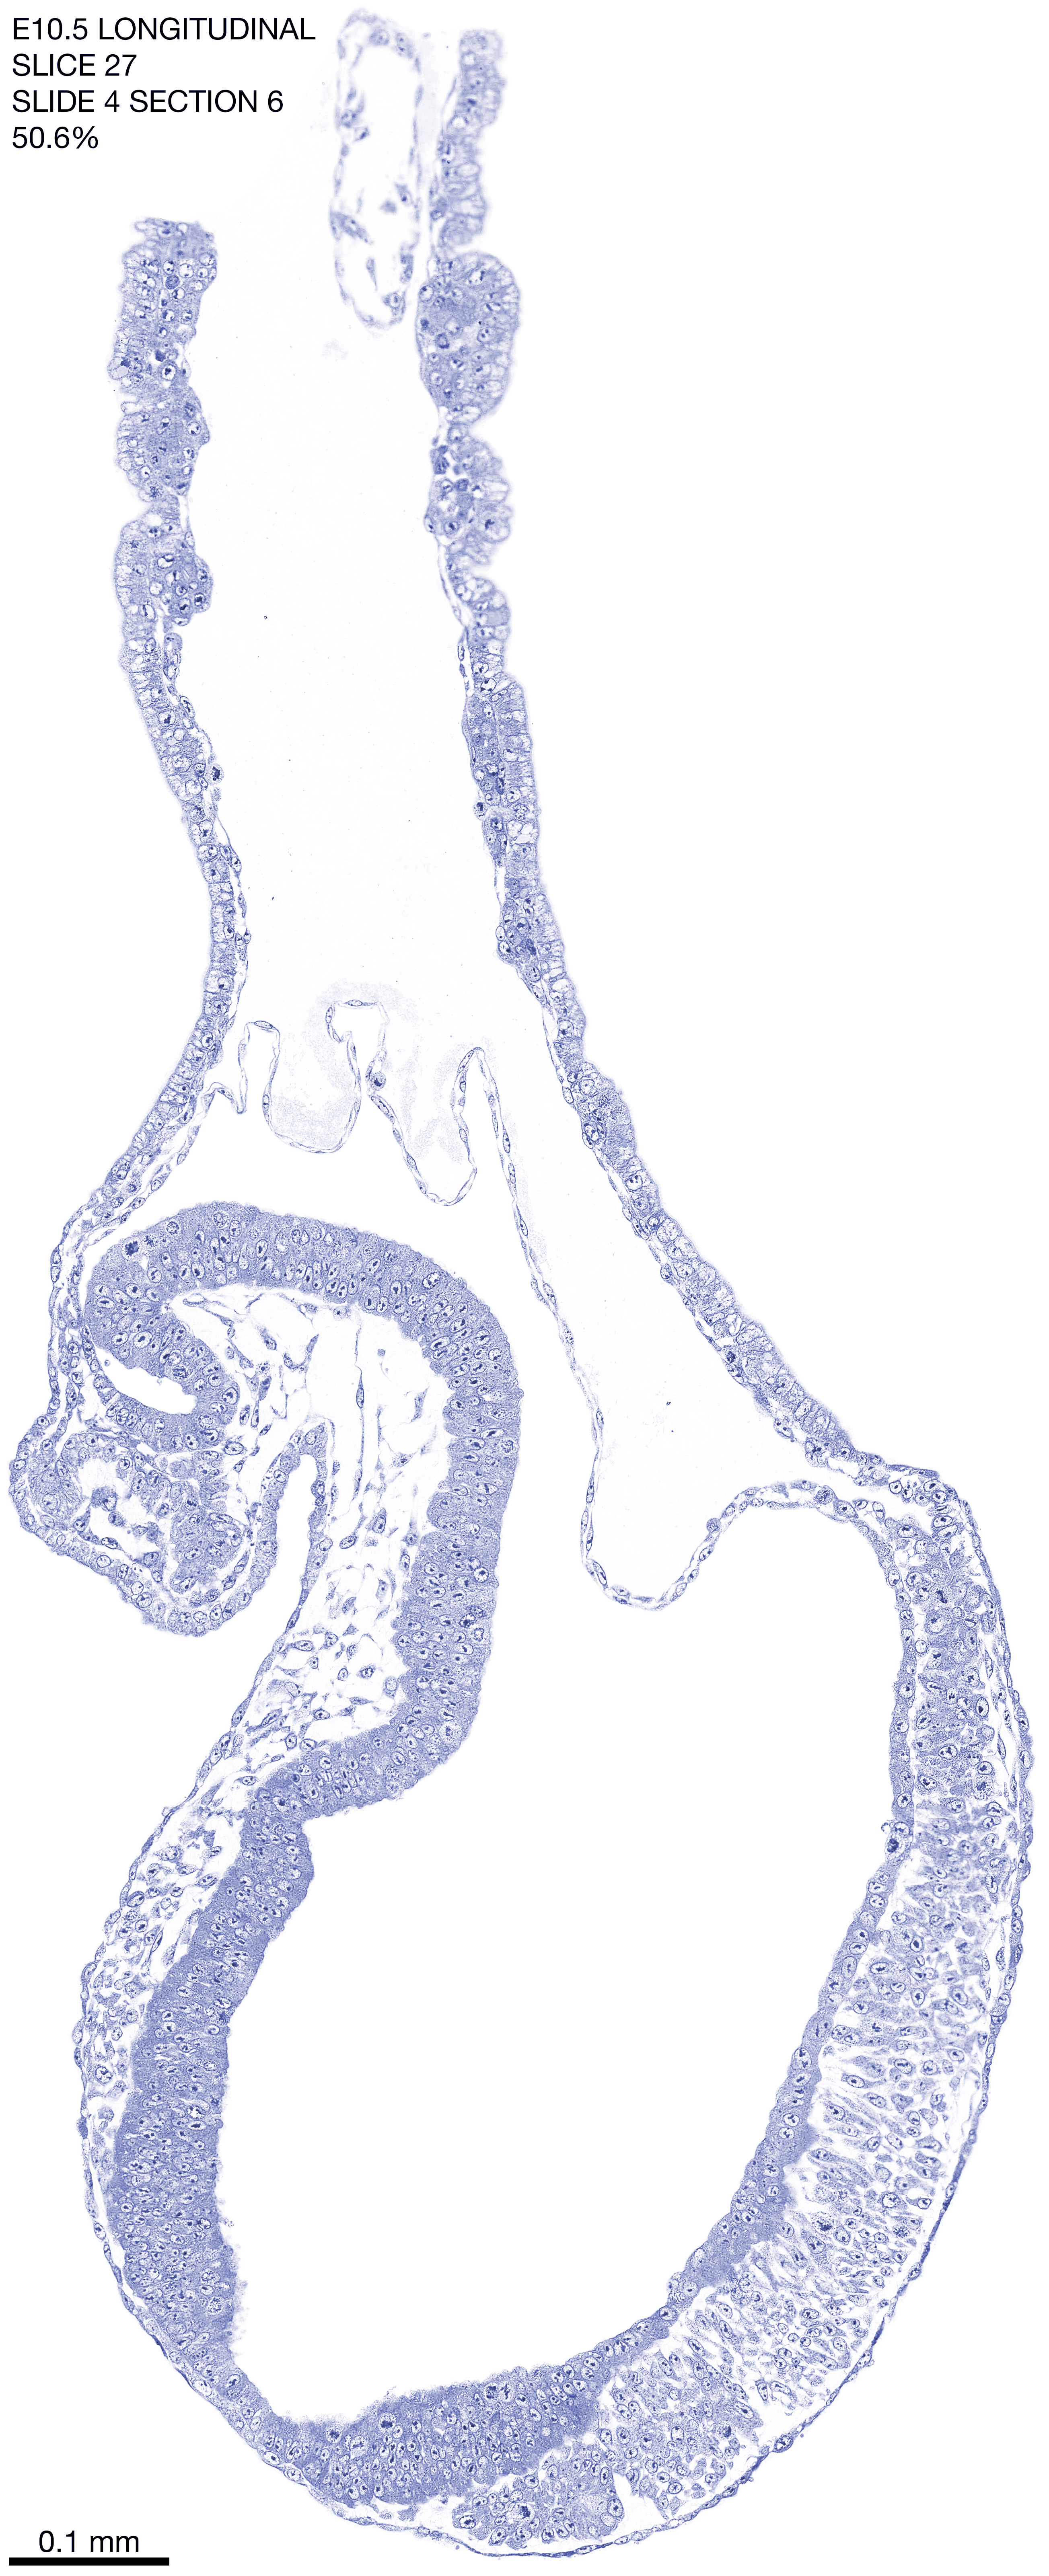

E10.5 Longitudianal Archive This page contains jpg files of ALL SLICES (each 3µm thick) that were scanned of the E10.5 longitudinally cut specimen. Download: Large | High Res Download: Large | High Res Download: Large | High Res Download: Large | High Res Download: Large | High Res Download: Large | High Res Download: Large | High Res Download: Large | High Res Download: Large | High Res Download: Large | High Res Download: Large | High Res Download: Large | High Res Download: Large | High Res Download: Large | High Res Download: Large | High Res Download: Large | High Res Download: Large | High Res Download: Large | High Res Download: Large | High Res Download: Large | High Res Download: Large | High Res Download: Large | High Res Download: Large | High Res Download: Large | High Res Download: Large | High Res Download: Large | High Res Download: Large | High Res Download: Large | High Res Download: Large | High Res Download: Large | High Res Download: Large | High Res Download: Large | High Res Download: Large | High Res Download: Large | High Res Download: Large | High Res Download: Large | High Res Download: Large | High Res Download: Large | High Res Download: Large | High Res Download: Large | High Res Download: Large | High Res Download: Large | High Res Download: Large | High Res Download: Large | High Res Download: Large | High Res Download: Large | High Res Download: Large | High Res Download: Large | High Res Download: Large | High Res Download: Large | High Res Download: Large | High Res Download: Large | High Res Download: Large | High Res Download: Large | High Res Download: Large | High Res Download: Large | High Res Download: Large | High Res Download: Large | High Res